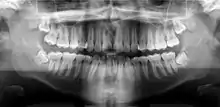

Orthopantomograms (OPTs) are used by health care professionals to provide information on:

- Impacted wisdom teeth diagnosis and treatment planning - the most common use is to determine the status of wisdom teeth and trauma to the jaws.

- Periodontal bone loss and periapical involvement.

- Finding the source of dental pain, and when carrying out tooth-by-tooth diagnosis.

- Assessment for the placement of dental implants

- Orthodontic assessment. pre and post operative

- Diagnosis of developmental anomalies such as cherubism, cleido cranial dysplasia

- Carcinoma in relation to the jaws

- Temporomandibular joint dysfunctions and ankylosis.

- Diagnosis of osteosarcoma, ameloblastoma, renal osteodystrophy affecting jaws and hypophosphatemia.

- Diagnosis, and pre- and post-surgical assessment of oral and maxillofacial trauma, e.g. dentoalveolar fractures and mandibular fractures.

- Salivary stones (Sialolithiasis).

- Other diagnostic and treatment applications.[2]